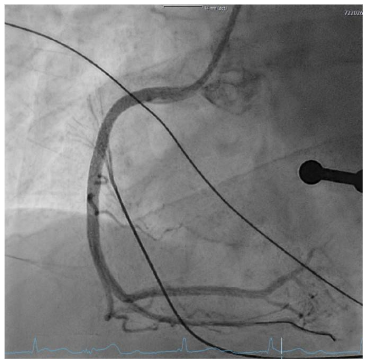

A 27-year-old patient presented with suspected ST-segment elevation myocardial infarction (STEMI). Approximately one hour prior to admission, the patient experienced onset of typical angina pectoris with accompanying vegetative symptoms (nausea and vomiting). Similar episodes had not occurred before. The patient’s medical history revealed regular or daily consumption of high-percentage alcohol, nicotine and cannabis. A few days before the event, the patient intended to consume nasal amphetamines, but due to a mix-up the substance consumed was heroin. No further substance use was reported. Furthermore, the patient had a tick bite approximately 10 years ago. The initial electrocardiogram (ECG) showed ST segment elevations in leads II, III, and avF, as well as a second-degree atrioventricular block (Mobitz type II) with a heart rate of approximately 70 beats/minute. Laboratory tests showed elevated cardiac biomarkers, with (troponin I 14.037 µg/l (cut-off value <0.045 µg/l) and CK-MB at 79 U/l (cut-off value <24U/l). Furthermore, the patient exhibited a flamboyant exanthema in large areas of the face with known atopic dermatitis. The patient reported of a pronounced stress response triggered by various problems in the work environment and social circle. After findings were reviewed in the Chest Pain Unit, based on the initial assessment, the patient was immediately transferred to the catheterization lab. The attending physician administered prehospital medication with aspirin and heparin. An emergency coronary angiography was performed, which revealed a single-vessel coronary disease with a subtotal occlusion of the right coronary artery (RCA) and high thrombus burden. During the procedure, the patient admitted that he had smoked marijuana the same morning. A primary stenting using a drug eluting stent (DES, Promus 4.0/32mm, Boston Scientific, Marlborough, Massachusetts) was performed, followed by stent optimization with balloon angioplasty. Complete reperfusion was documented immediately without evidence of remaining dissection or vascular injury. The placement of a temporary pacemaker was not necessary and the patient was transferred to our intensive care unit. Post-interventional follow-up showed no evidence of atrioventricular block and complete ST resolution on the following day. Dual antiplatelet therapy with acetylsalicylic acid and ticagrelor was initiated. On the following day, there was a slight increase in troponin I to a maximum of 18.469 µg/l, after which it then decreased, similarly CK values decreased. In addition, there was a slight increase in inflammatory markers, (CRP 41 mg/l, leukocytes 14.000/µl). LDL cholesterol was significantly elevated at 150 mg/dl (fasting, the following day), while HDL cholesterol was within the normal range at 40 mg/dl and triglycerides were at 145 mg/dl, Lipoprotein (a) 6.3 mg/dl. The urinary toxicology test showed a qualitative detection of benzodiazepines, cannabinoids, and opioids. Interestingly, serologically, IgM antibodies against Borrelia burgdorferi were detected without IgG antibodies. Further diagnostic workup included transthoracic and transesophageal echocardiography, which showed a severely reduced left ventricular ejection fraction (LVEF) of 29% by Simpson (biplane analysis), as well as an inferior inferolateral akinesia. Additionally, a floating structure measuring approximately 8x8mm was observed attached to the inferolateral wall, suggesting a ventricular thrombus. To further confirm the diagnosis and investigate the reduced LVEF, a cardiac magnetic resonance imaging (MRI) was scheduled. The possibility of providing a life vest was discussed until a decision regarding an implantable cardioverter-defibrillator (ICD) was made. Unfortunately, the patient declined further tests and treatments and left the hospital against our advice.